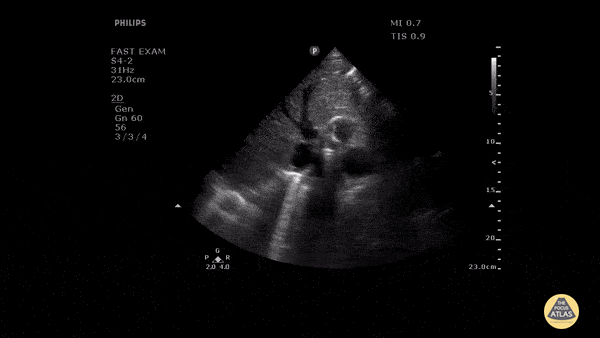

Aorta - Faint Dissection Flap in Descending Aorta

Patient presented with severe chest pain and concerning ECG without STEMI. A faint dissection flap can be seen in the aorta on this transverse view in the subcostal region. Image courtesy of Robert Jones DO, FACEP @RJonesSonoEM Director, Emergency Ultrasound; MetroHealth Medical Center; Professor, Case Western Reserve Medical School, Cleveland, OH View his original post here